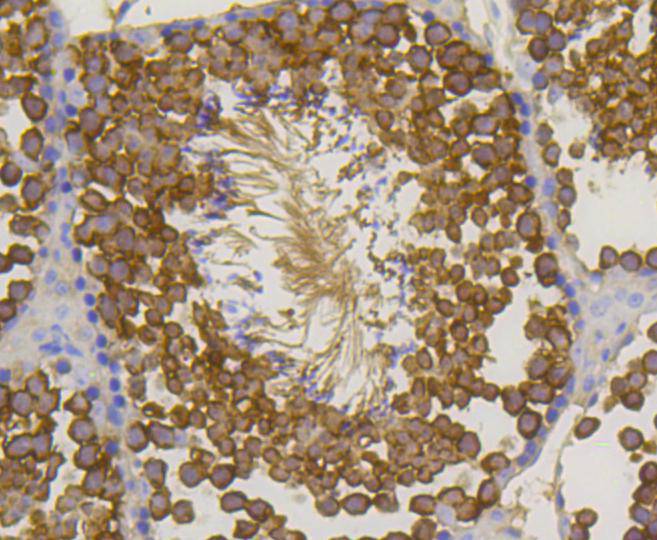

Immunohistochemical analysis of paraffin-embedded mouse testis tissue using anti-Hsp70 antibody. Counter stained with hematoxylin.